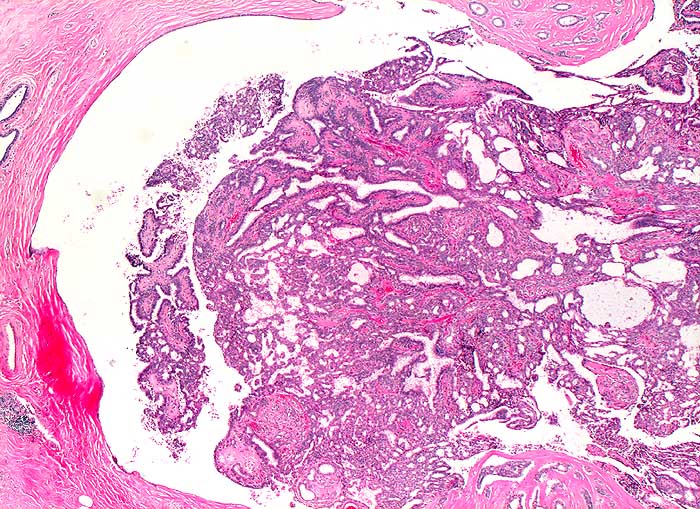

Milchgangpapillom

benigner Tumor

Papilläre Zellverbände oder Zellballen auf zystischem Hintergrund sprechen für eine papilläre Neoplasie. Feinnadelpunktate von papillären Neoplasien sind oft blutig. Gutartige Papillome gleichen zytologisch Fibroadenomen. Geringere oder fehlende Stromakomponente, Zystenbildung, Zellballen, Einblutung und klinische Präsentation in Form einer einseitigen hämorrhagischer Mamillensekretion sprechen für ein Papillom. Sowohl benigne als auch maligne papilläre Neoplasien können ein relativ blandes uniformes Zellbild zeigen. Papilläre Karzinome erscheinen oft monomorpher als gutartige Papillome. Hohe Zellularität, zahlreiche Einzelzellen und die Abwesenheit benigner Zellen (apokrine Zellen, Myoepithelien) sprechen eher für ein papilläres Karzinom. Meist handelt es sich dabei um nicht invasive intraduktale Karzinome.